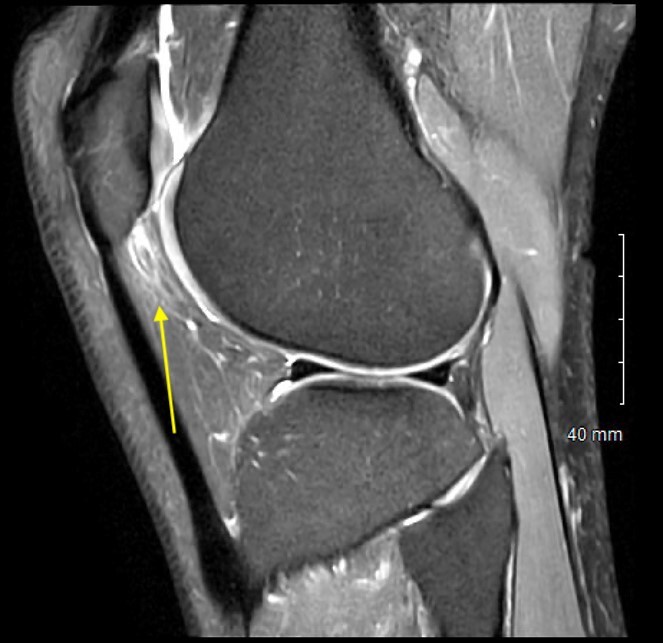

On exam she had pain to palpation of the anterolateral fat pat, with mild patellofemoral crepitus. Her range of motion was 0-130 degrees. Ligamentous exam was stable with full strength in quadriceps and hamstrings on manual muscle testing. Magnetic Resonance Imaging (MRI) demonstrated subtle thinning of the lateral patellar articular cartilage, fibrosis of the infrapatellar fat pad, and distension of the infrapatellar bursa (Figure 1). Otherwise, her MRI was unremarkable.

On physical exam he had no pain with patellar grind test but had pronounced pain to palpation of the infrapatellar fat pad. He had painless range of motion of 0-130 degrees and had no J sign and did not demonstrate patellar maltracking. Ligamentous exam was stable and neurovascular exam was intact. His MRI demonstrated hypertrophy and swelling of the infrapatellar fat pad (Figure 3). Given his history and imaging findings a diagnostic fat pad injection was chosen as the initial course of treatment. Following injection, the patient underwent treadmill running and noted a near complete resolution of symptoms and as such the decision was made to proceed with arthroscopic fat pad resection, starting with the more symptomatic right side.